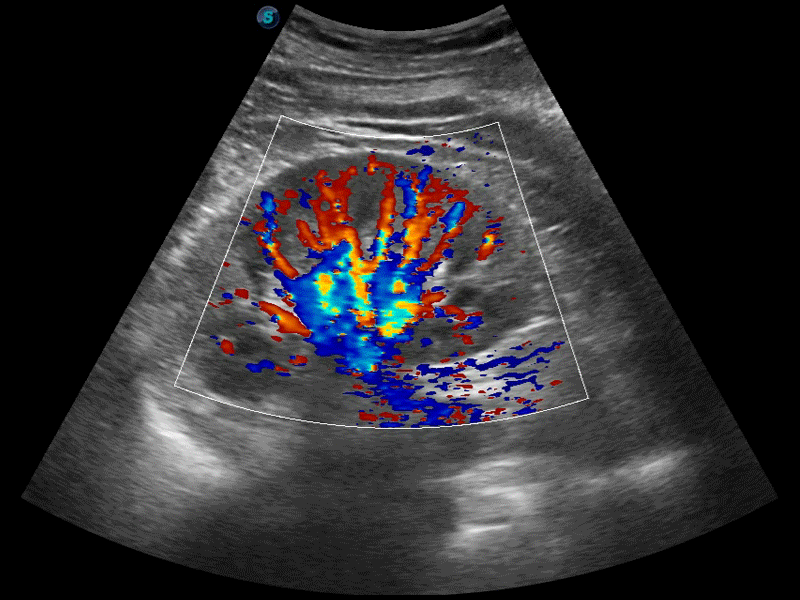

高分辨率血流成像技术提高了对低速血流信号的检测能力。在提高空间分辨率的同时,也克服了血流外溢现象,为用户提供更加真实的血流动力学信息。

凸阵、线阵和相控阵探头进行实时扫描时,开启扩展成像模式,可以扩展超声图像视野,以便更完整地查看大的病灶或组织器官的解剖结构。

通过色彩血流和实时宽景相结合,可观察到完整的静脉或动脉的血流,方便医生检查。实时扫查过程中,如有任何操作失误也可以很容易地进行回扫擦除,而不会中断扫查。